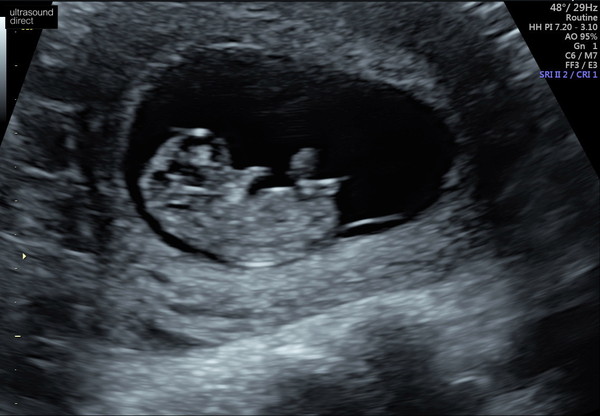

Just had our first scan as my nhs one is booked for 13+4 and I couldn't wait that long! Seems to have lots of energy .. have a feeling this one will be keeping me up at night 😂